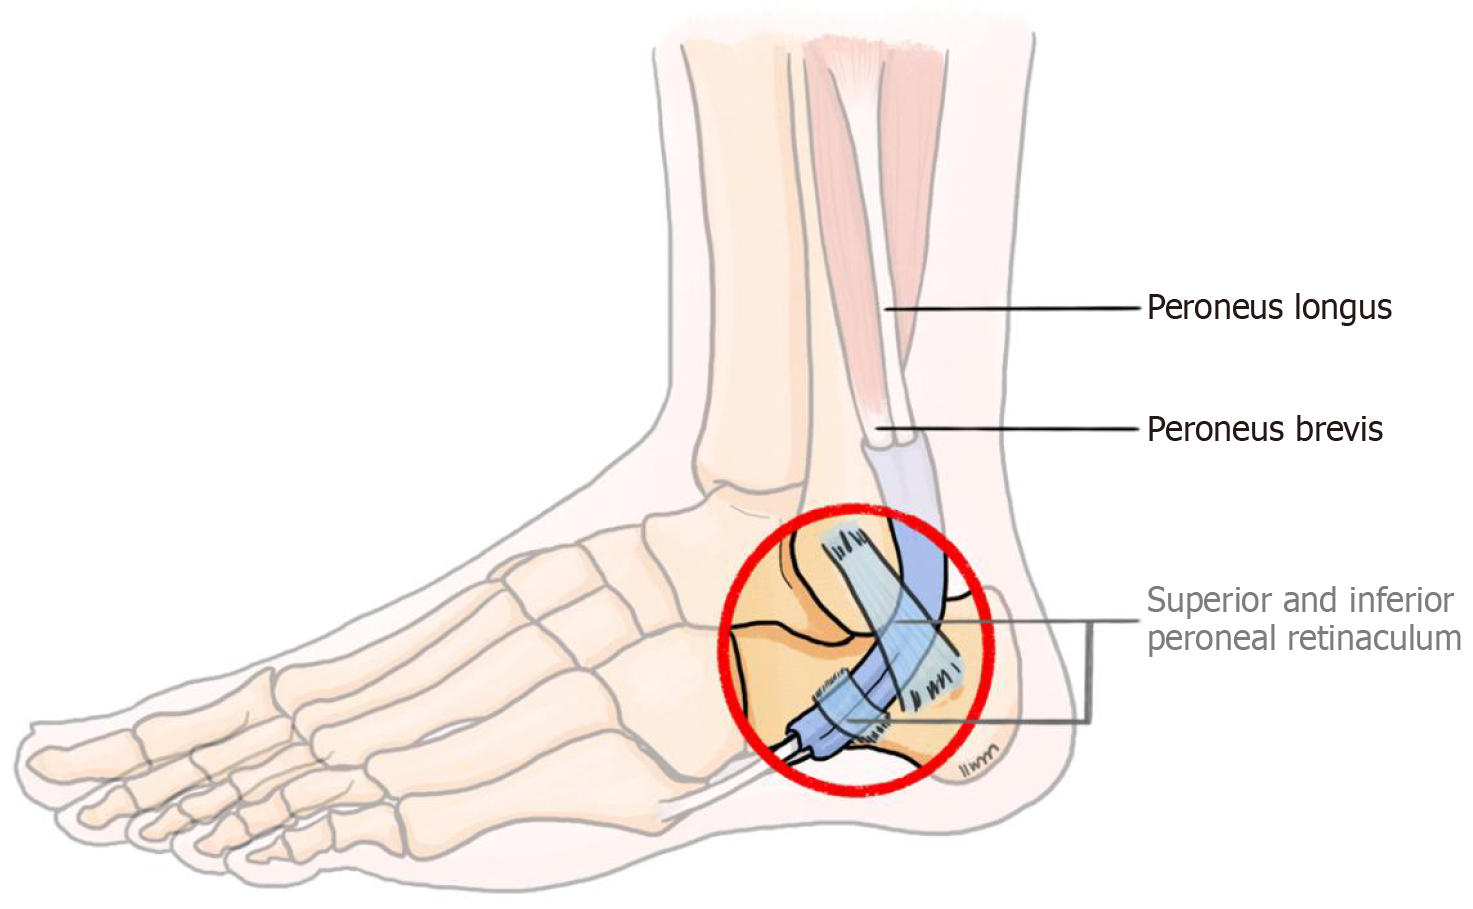

Figure 1 Illustration of structures contributing to lateral ankle snapping: Peroneal tendons beneath the superior and inferior peroneal retinacula.